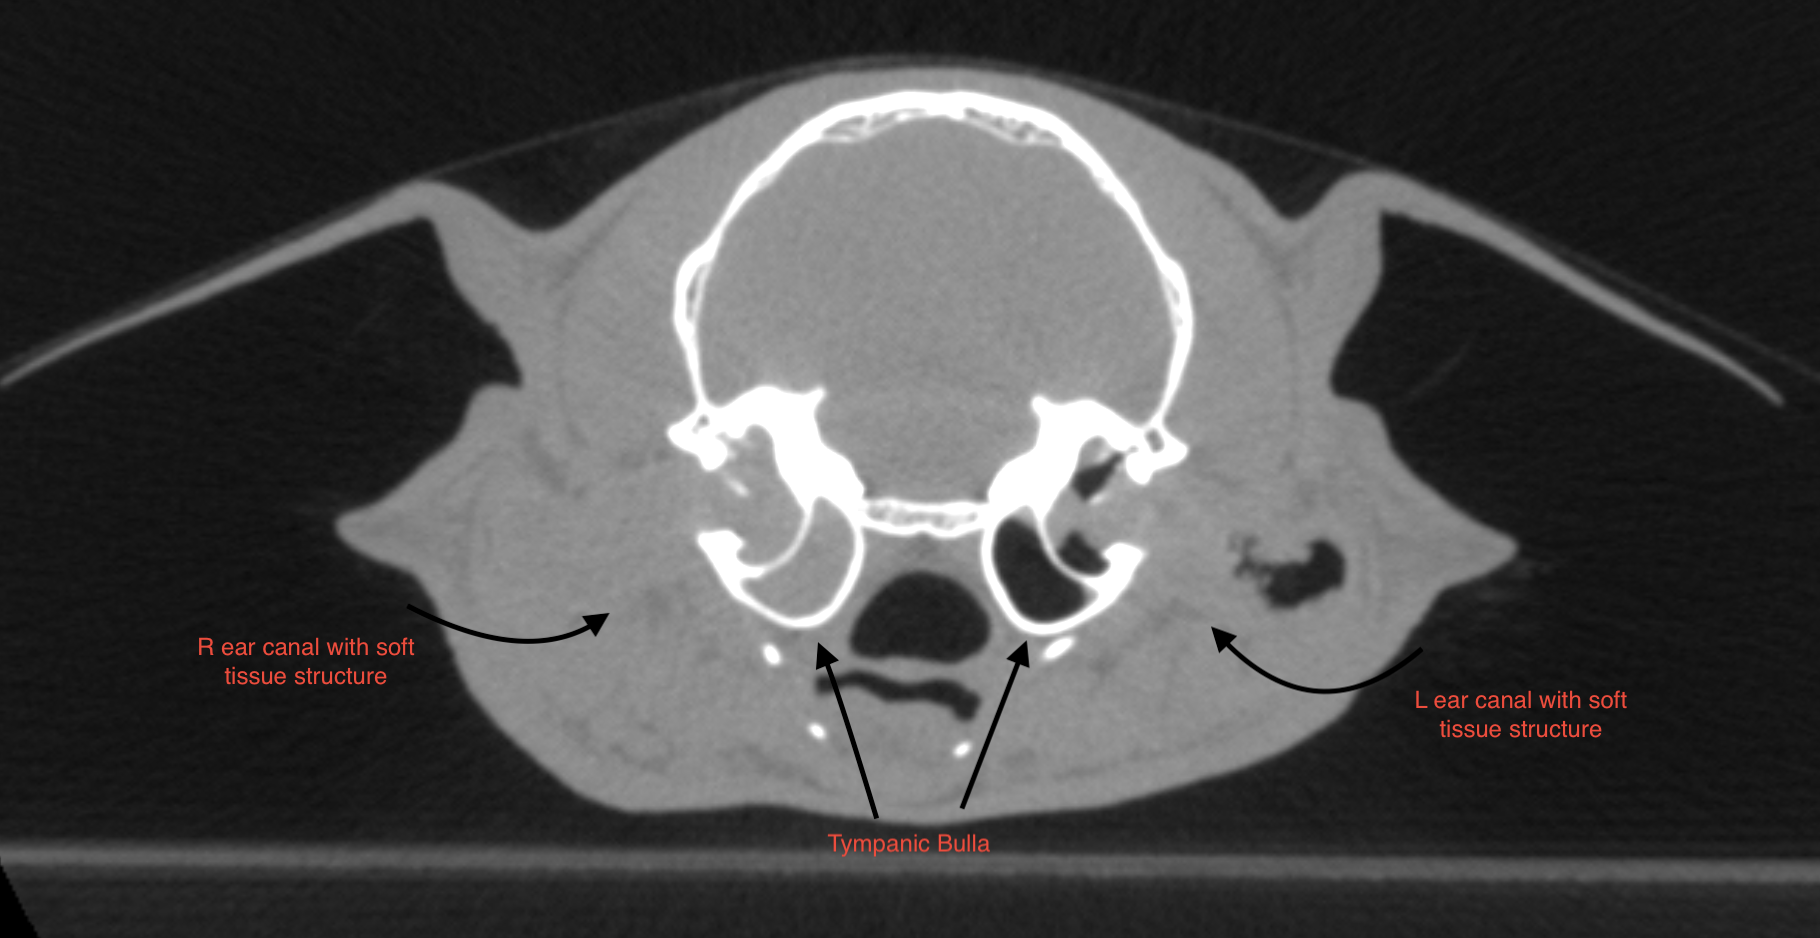

On the left, a CT image showing the measurements of the soft tissue structures within the ear canals.

In the right external auditory canal, a large, elongated soft-tissue-attenuation structure with mild peripheral contrast enhancement is observed in the horizontal portion, completely obstructing the lumen and protruding into the region of the tympanic membrane. A small amount of adjacent hypoattenuating fluid is present. The lesion measures approximately 1.3 × 0.57 cm. Moderate hypoattenuating fluid accumulation with peripheral enhancement is noted within the right tympanic bulla, with preservation of the bony wall.

In the left external auditory canal, a moderately sized, elongated soft-tissue–attenuation structure with contrast enhancement is present in the horizontal portion, smaller compared with the right side, and protruding into the region of the tympanic membrane.

Mild adjacent hypoattenuating fluid retention is also observed. The lesion measures approximately 1.0 × 0.46 cm. A discrete amount of hypoattenuating fluid is present within the left tympanic bulla, with preservation of the bony wall.

• Right external auditory canal exhibits a large soft-tissue–attenuation structure with peripheral contrast enhancement, obstructing the lumen, associated with fluid in the right tympanic bulla. Differential diagnoses include aural polyp, inflammatory lesion, concurrent otitis media, or fluid retention.

• Left external auditory canal exhibits a large soft-tissue–attenuation structure, associated with mild fluid retention and discrete fluid in the left tympanic bulla. Differential diagnoses include aural polyp, inflammatory lesion, and discrete fluid retention within the ipsilateral tympanic bulla.